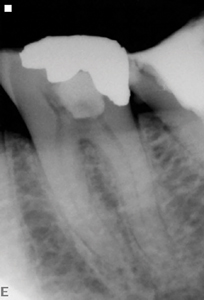

Agreeing to my definitions, I chose to survey 10 respected endodontists who have proofread my condensing of their answers and have selected pre- and post-treatment images that they believe radiographically represent their trenchant visual expression of the Endodontic Triad. (Fig. 2) Below, in alphabetical order, are their answers to my survey. Their techniques or armamentaria were copied and pasted from the survey, and where a quotable opinion was offered, it appears in quotes.

Fig. 2A

Fig. 2B

Fig. 2C

Fig. 2D

Fig. 2E

Fig. 2F

Fig. 2G

Fig. 2H

Fig. 2I

Fig. 2J

Fig. 2K

Fig. 2L

Fig. 2M

Fig. 2N

Fig. 2O

Fig. 2P

Fig. 2Q

Fig. 2R

Fig. 2S

Fig. 2T